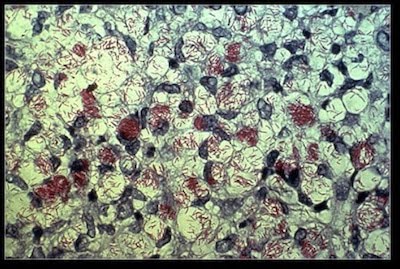

Є насправді п’ять різних видів лейкоцитів, всі з конкретними завданнями. Ці п’ять видів групуються в дві основні категорії: гранулоцити (нейтрофіли, еозинофіли, базофіли) і агранулоцити (лімфоцити та моноцити). За своєю природою вони прозорі, й повинні бути пофарбовані для мікроскопічного спостереження. Лімфоцити трохи більше еритроцитів і є другим найбільш поширеним типом лейкоцитів. Вони мають невелике, темне ядро з невеликим обідком цитоплазми. За допомогою мікроскопа ви часто бачите тільки ядро або навколишнє тонке біле кільце.

Еозинофіли є рідкісними фагоцитарними клітинами, але необхідні для боротьби з паразитами, особливо червами. Вони мають дволопатеві ядра, і їхні гранули забарвлюються червоним кольором із плямою Райта, звідки і їхня назва («еозин» означає «червоний»). Вони зменшують запалення. Вони також збільшуються в кількості під час паразитарних інфекцій. Еозинофіли виділяють ферменти, які вбивають або контролюють паразитів, таких як малярійні найпростіші, стрічкові черви, круглі черви і двовустки. Еозинофіли також мають деякий вплив на Plasmodium falciparum, причину злоякісної малярії. Проте їхня дія менш ефективна, ніж їхня здатність фагоцитувати червів. Часто потребується десятки еозинофілів для того щоб атакувати, фагоцитувати та вбивати паразитів (Робертс, Яновий-мол. та Надлер 2013).